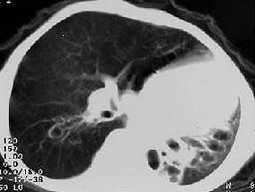

[单选题]女,8岁,如图所示,最可能诊断为()A .左下肺不张B .左下肺隔离症C .左肺发育不全D .左下肺支气管扩张E .左下肺支气管囊肿